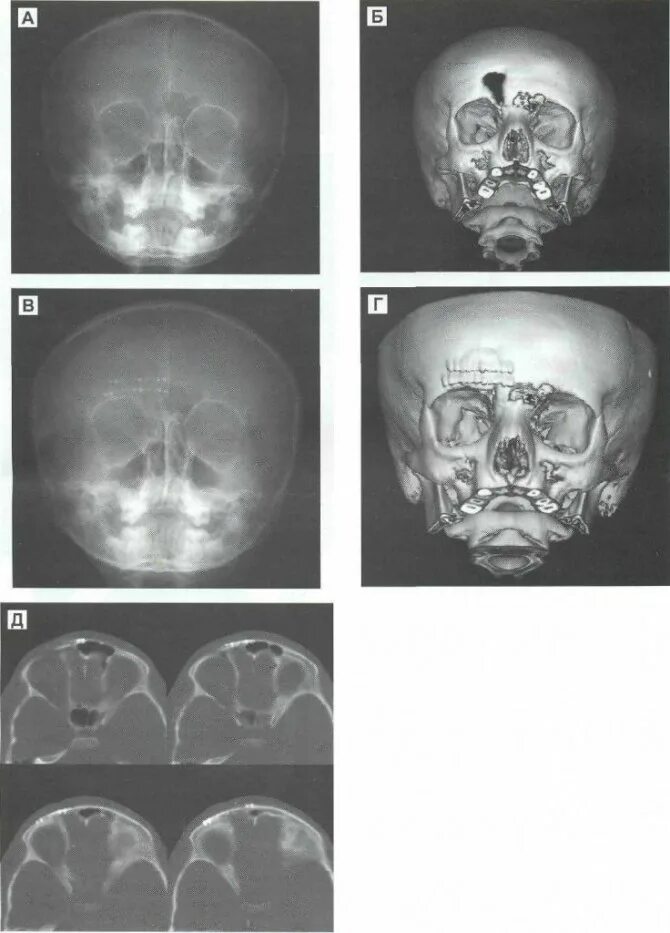

Перелом стенки левой орбиты